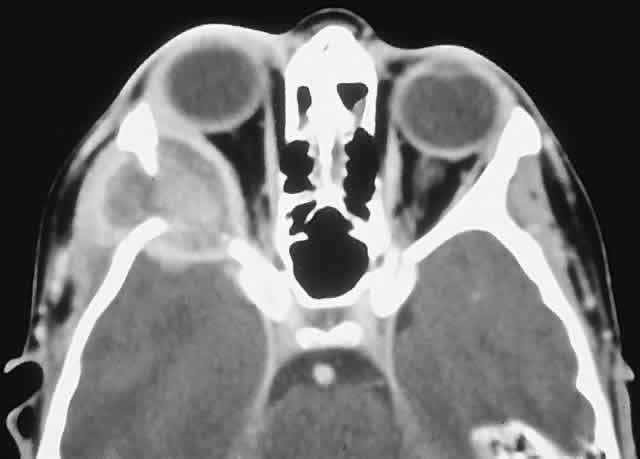

| The above clinical patterns correlate reasonably well with the following